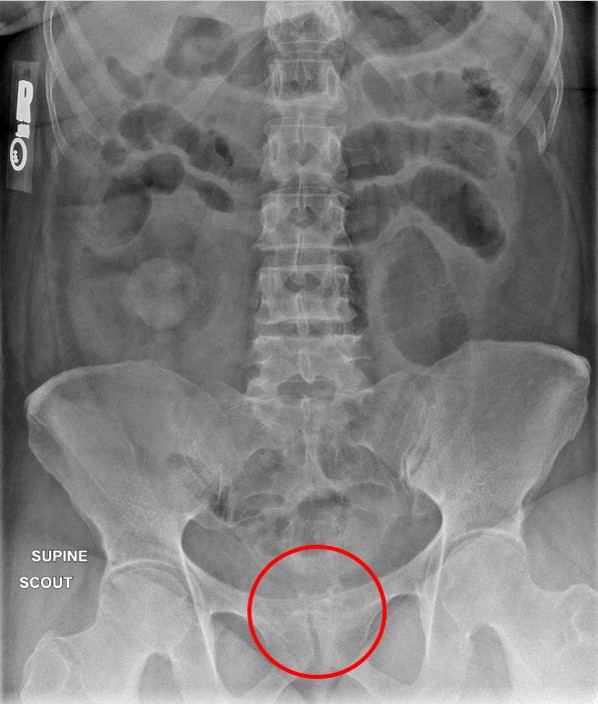

- During this examination, special attention should be paid to the anatomosis. When reviewing the scout image, look for surgical chain sutures in the pelvis

(key image 20)

(key image 21).